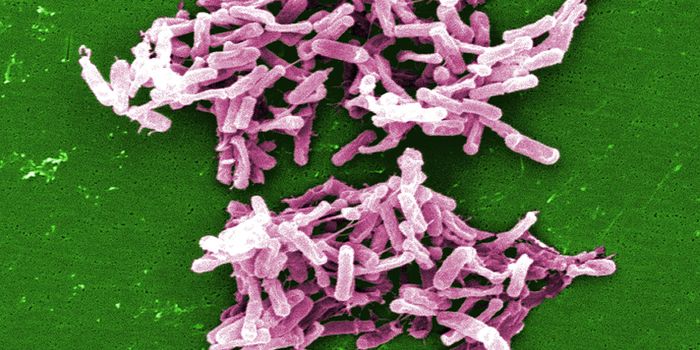

FEB 27, 2015Health & MedicineClostridium difficile (C. difficile, or C. diff) caused almost half a million infections among patients in the United St ...

FEB 27, 2015Health & MedicineATLANTA -- A nasty intestinal bug sickens nearly twice as many Americans each year as was previously thought, according ...